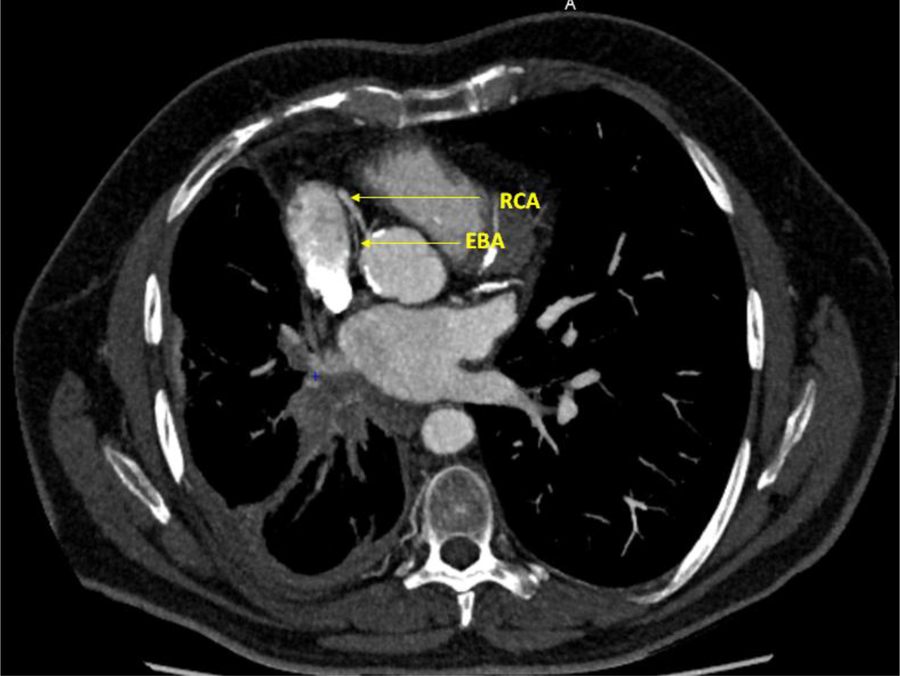

Immunotherapy was continued. The latest tumor assessment in January 2022 showed a stable disease. We asked the radiologists to perform a CT scan to determine the site of the fistula (Figures 2, 3).

Figure 3

Axial section, right coronary artery (RCA) and ectopic bronchial artery (EBA) (coroscan).